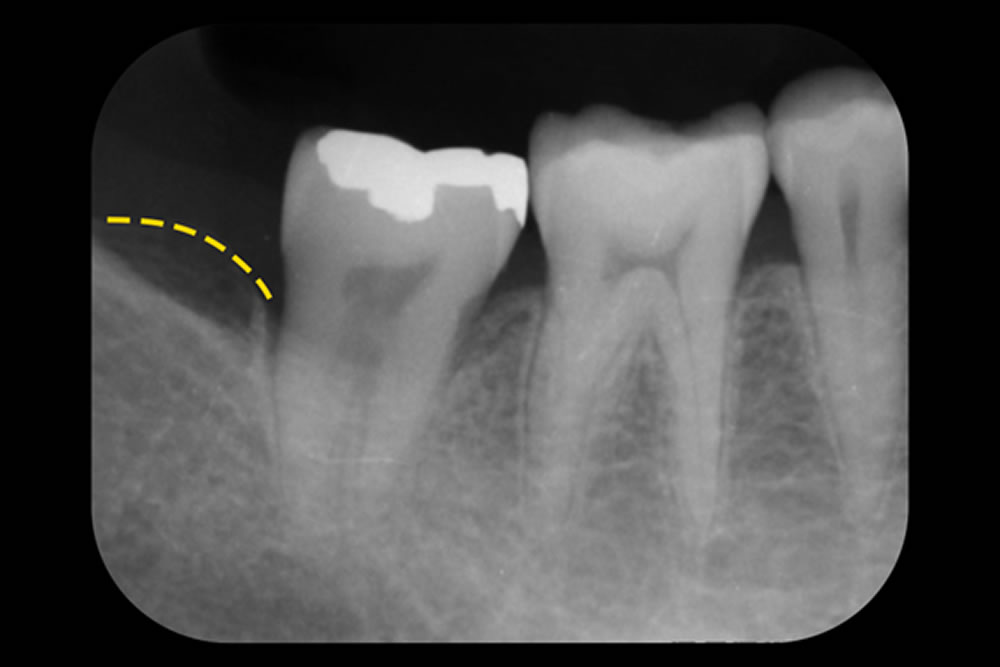

レントゲンでは、歯の周囲の骨が部分的に失われる「骨内欠損」が確認されました。そこで今回は、歯ぐきを一切切らずに行う非外科的治療「MINST(Minimally Invasive Non-Surgical Technique)」を採用しました。この方法では、歯肉溝(歯と歯ぐきのすき間)からマイクロスコープ(顕微鏡)で直接アプローチし、歯ぐきや組織へのダメージを最小限に抑えながら治療を行います。